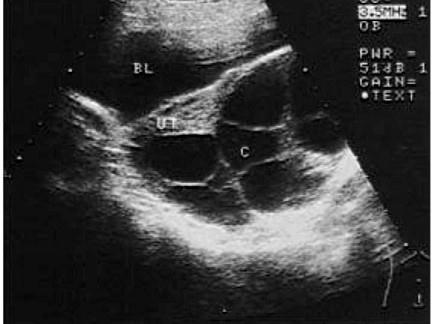

问题 女性,28岁,停经3个月,阴道不规则出血20余天。妇检:子宫体积大于停经周数,宫旁触及囊性肿块。血HCG2200μg/ml,结合超声图像,最可能的诊断为?(?)

选项 A.囊腺癌 B.囊腺瘤 C.黄体囊肿 D.黄素囊肿 E.皮样囊肿

答案 D